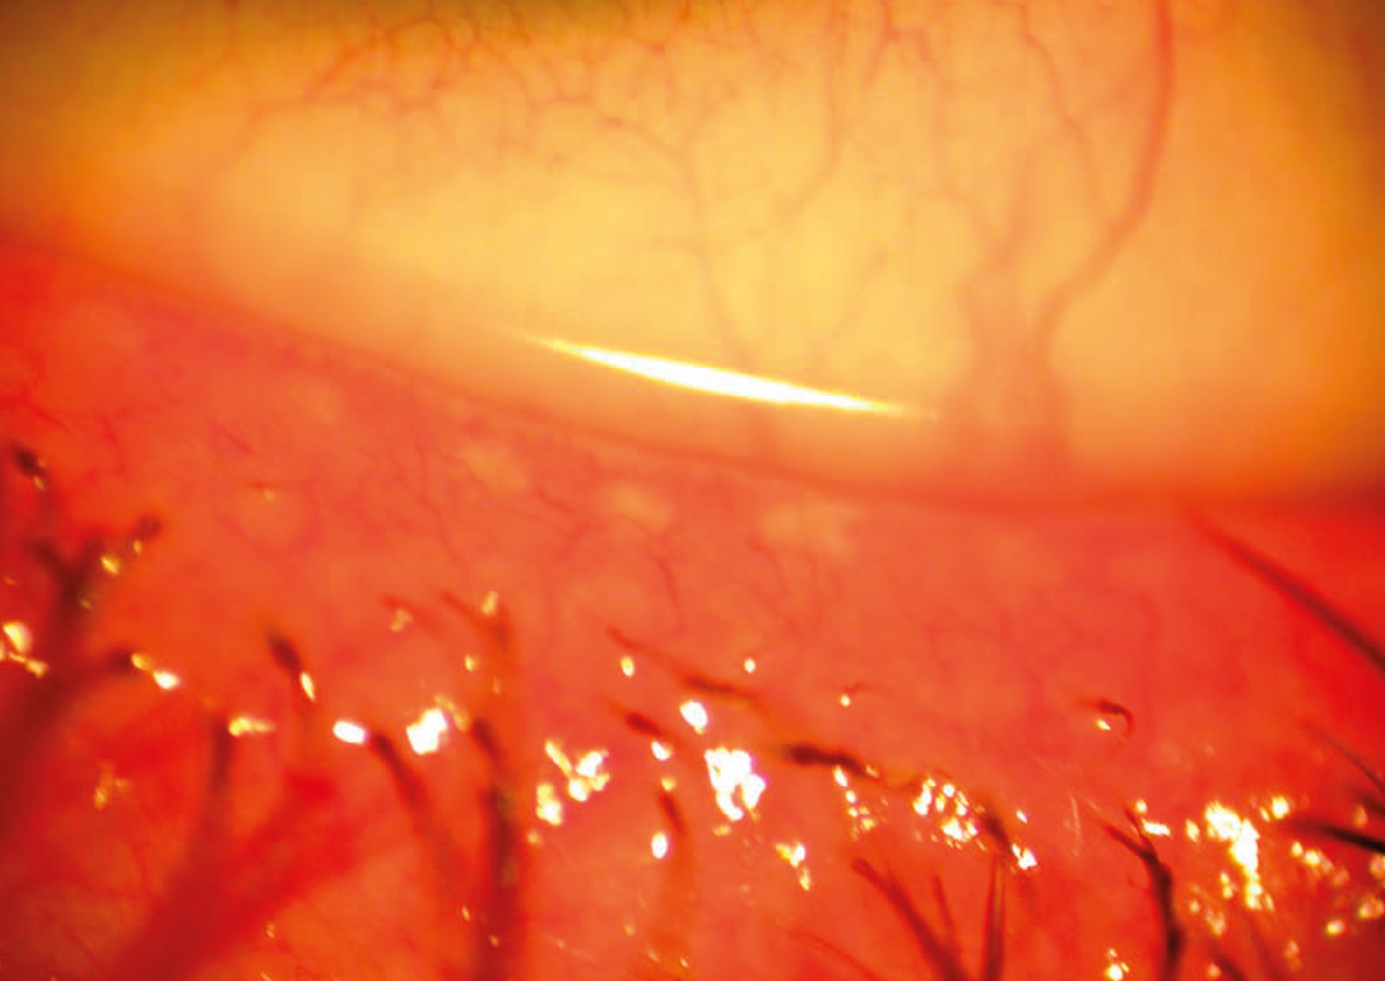

Figure 2. Le trabéculum juxtacanaliculaire dans la pince lors d’une sclérectomie profonde. C’est ce trabéculum qui offre 80 % de la résistance à l’écoulement de l’humeur aqueuse par la voie trabéculaire.